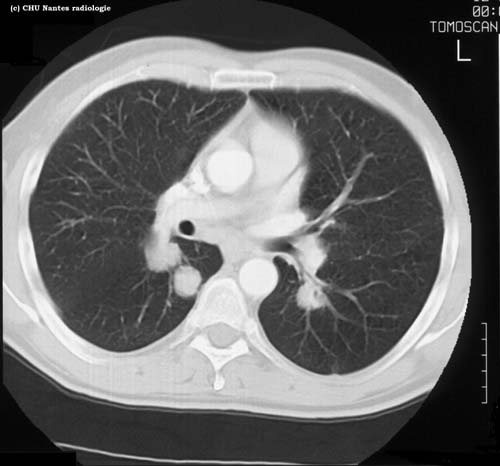

Lésions nodulaires : coupe

TDM

légendes

niveau de la coupe